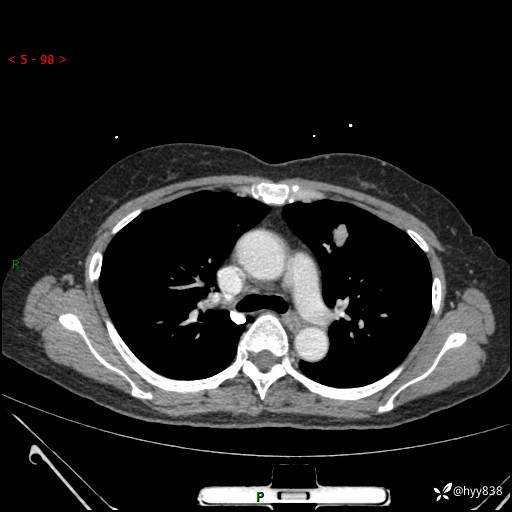

54岁/女,发现肺占位1天。观其形态和强化,术前我信心十足,术后我---结果公布~

【患者信息】:54岁/女

【主诉】:发现肺占位1天

【现病史及既往史】:患者2023.10.23体检发现肺占位:,2023.10.23当地区中心卫生院胸腹部CT:1.左肺上叶结节,考虑为占位可能;2.肝脏小囊肿灶;3.子宫左侧附件区畸胎瘤;无咳嗽咳痰,无恶心呕吐,无发热,无胸闷胸痛等不适;现患者为求进一步诊治来我院,门诊以“肺占位”收入我科。 患者自起病以来,精神饮食睡眠一般,大小便正常,体力体重无明显下降。

【检查】:胸部CT增强(外院平扫)